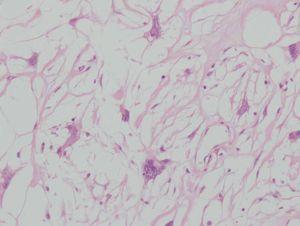

Histológicamente se observa una tumoración bien delimitada localizada en la dermis (fig. 1). El tumor muestra moderada cantidad de material mixoide entre tejido colágeno laxo. Entre las fibras de colágeno se observan células fusiformes, estrelladas y numerosas células gigantes multinucledas (fig. 2). Algunas de éstas tienen núcleos grandes, pleomórficos, hipercromáticos, con un pequeño nucleolo visible (fig. 3). Se observa escaso número de mitosis. La epidermis no muestra particularidades.

Fig. 2.--Tumor fusocelular con abundante matriz mixoide (hemato-xilina-eosina, 100).